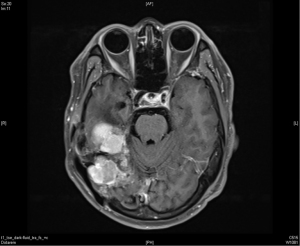

In April 2015, the patient took another course of radiotherapy as fractionated schedule of 5,940 cGy in 33 fractions, with 180 cGy in one fraction per day, 5 days a week, due to recurrence again nearby the previous tumor bed (Figure 3). The treatment volume of radiotherapy included the gross recurrent tumor with perifocal edematous change. This time, the recurrent tumor was under control and stable for about one and half year (Figure 4).